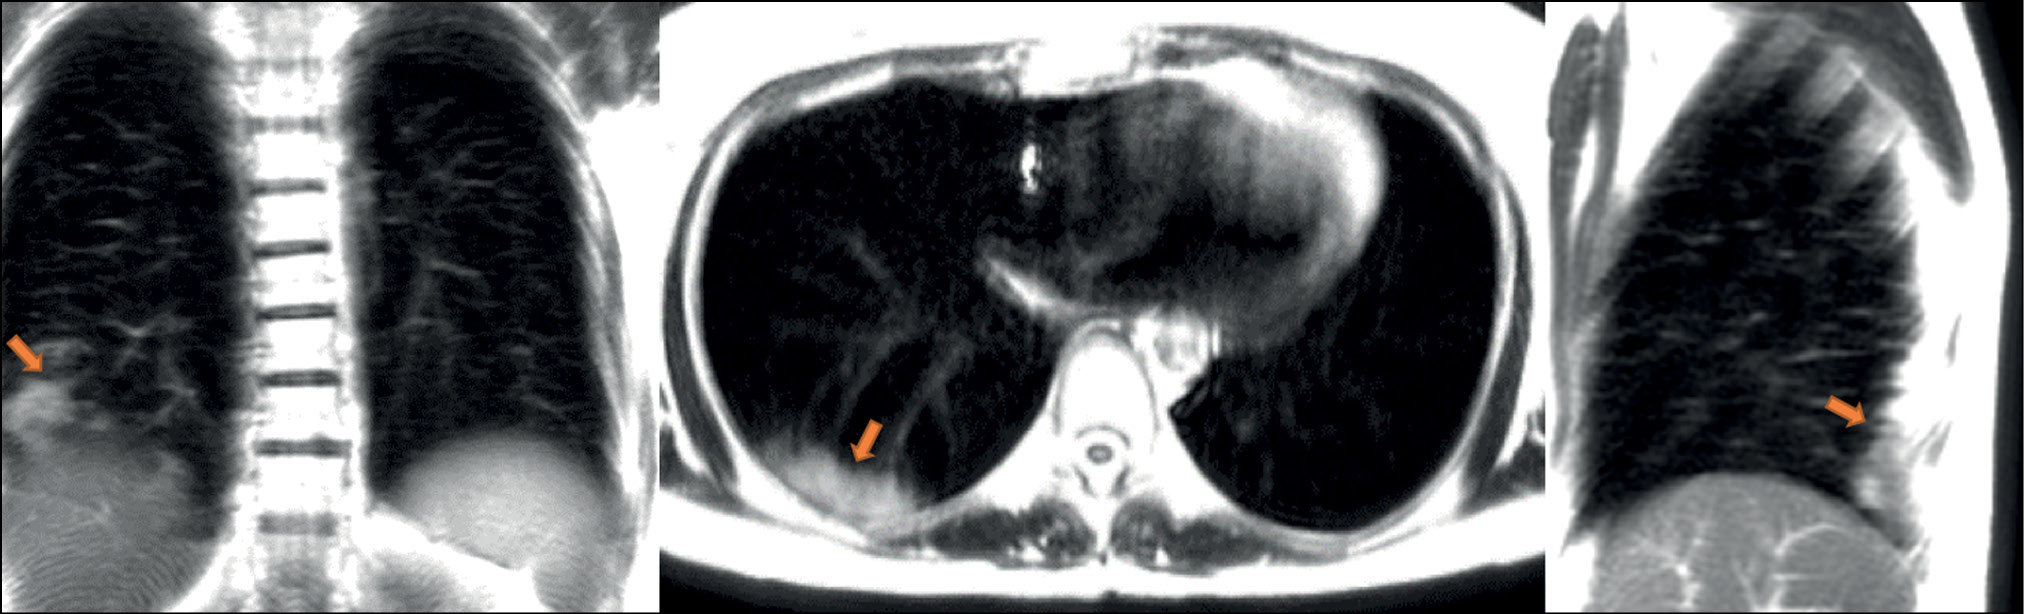

A patient (female, 45 years old) presented to the clinic on the fifth day after the onset of dry cough and mild fever up to 37.5°С. Dynamic lung MRI in the coronal plane (Fig. 1) showed an area of hyperintense signal in the lower lobe of the right lung (S9–S10), interpreted as an area of central induration (more intense signal) with a surrounding “cloudy sky” (less intense signal) during inhalation. A hyperintense signal was found in the corresponding area in the axial and sagittal planes, indicating consolidation with a “cloudy sky” along the edge of the area. At the end of exhalation, increased signal intensity was observed in the described area in the coronal plane (Fig. 2) with decreased visual size of the affected areas due to lung tissue contraction. During exhalation, no changes in signal intensity were observed in the axial and sagittal planes.

Figure 1. Dynamic magnetic resonance imaging of the lungs during inhalation in the coronal, axial, and sagittal planes. In the axial and sagittal planes, arrows point to areas of compaction. In the coronal plane, the arrow points to a “cloudy sky” (S9–S10).